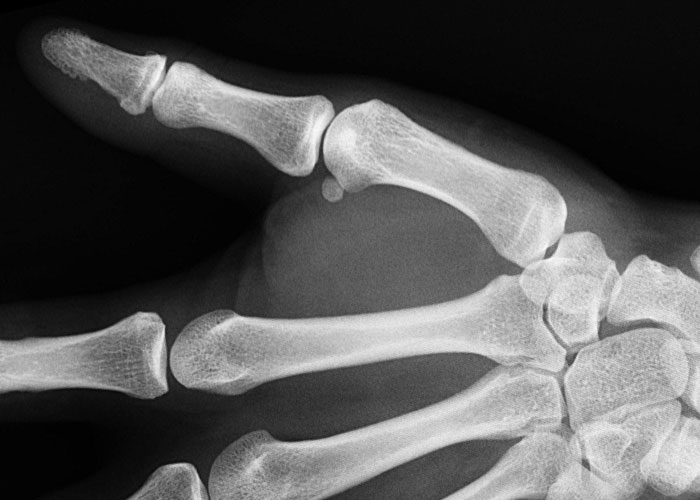

#34

I have offsetting birth defects in my hand. I inherited polydactyl genes from my mom and missing fingy genes from my dad. I have 10 fingers, but they’re not normal.

My right hand has 2 ring fingers and no pinky. Looks almost totally normal til you X ray it.

(Edit- The key difference between your pinky and other fingers is that the pinky shares a ~~knuckle~~ tendon with the ring finger. Thats why you can’t fold your pinky flat without also bending your ring finger in a little. I however can make a fist with only my “pinky” no problem.).